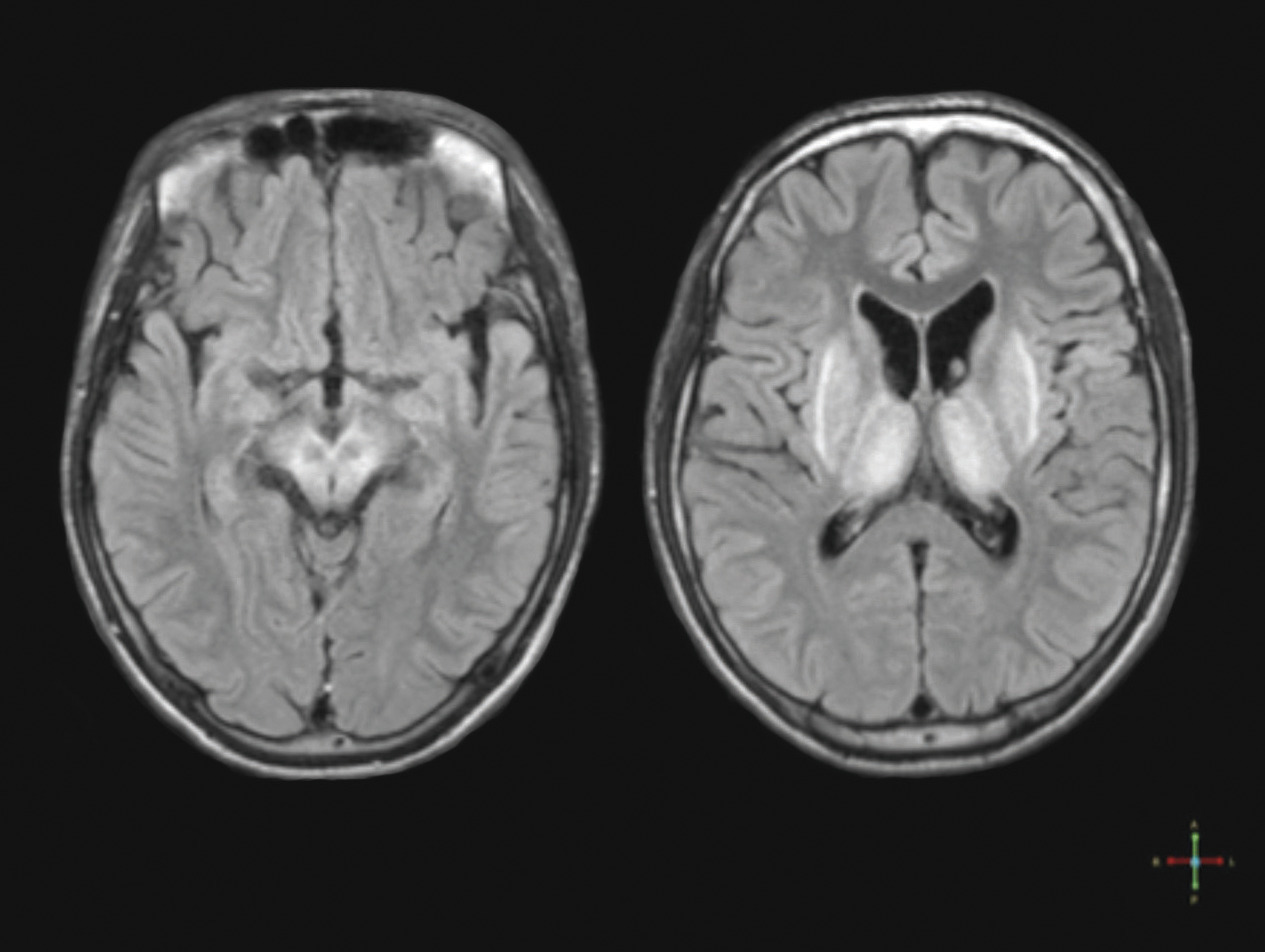

➜ la réalisation d’une IRM cérébrale (figure ci-dessus) qui dans les formes neurologiques est toujours anormale : hypersignaux T2 et FLAIR localisés aux noyaux gris centraux, au thalamus, au mésencéphale, voire au noyau dentelé ;